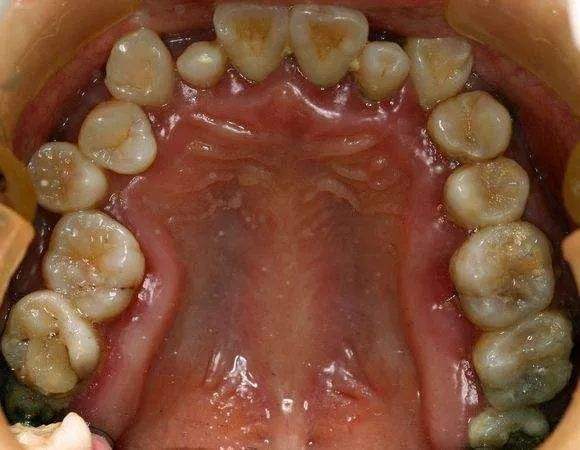

有一个来自互联网上的例子:三十多岁的小伙子牙周炎的最终归宿——全口牙松动,拔除。在口腔大夫那里,这些病例已经司空见惯了,一句话形容:看起来,他们一颗牙也不缺,其实,已经一颗牙也不在了!简直触目惊心!

牙周炎患者的就诊率低,因素绝不是单一的,当牙周炎患者出现多数牙松动后,有一种观念非常普遍——等牙全部掉光了再镶一口假牙。殊不知,全*活口**动义齿,功能比天然牙相差一大截,咀嚼效力并不高,使用也不方便,当然,全口种植义齿也是一种选择(如图),可以较好地恢复咀嚼功能,然而,并不是每个无牙患者,都拥有“口腔里开一辆奔驰”的财力。